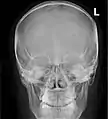

Paranasal sinuses radiograph (occipitomental)